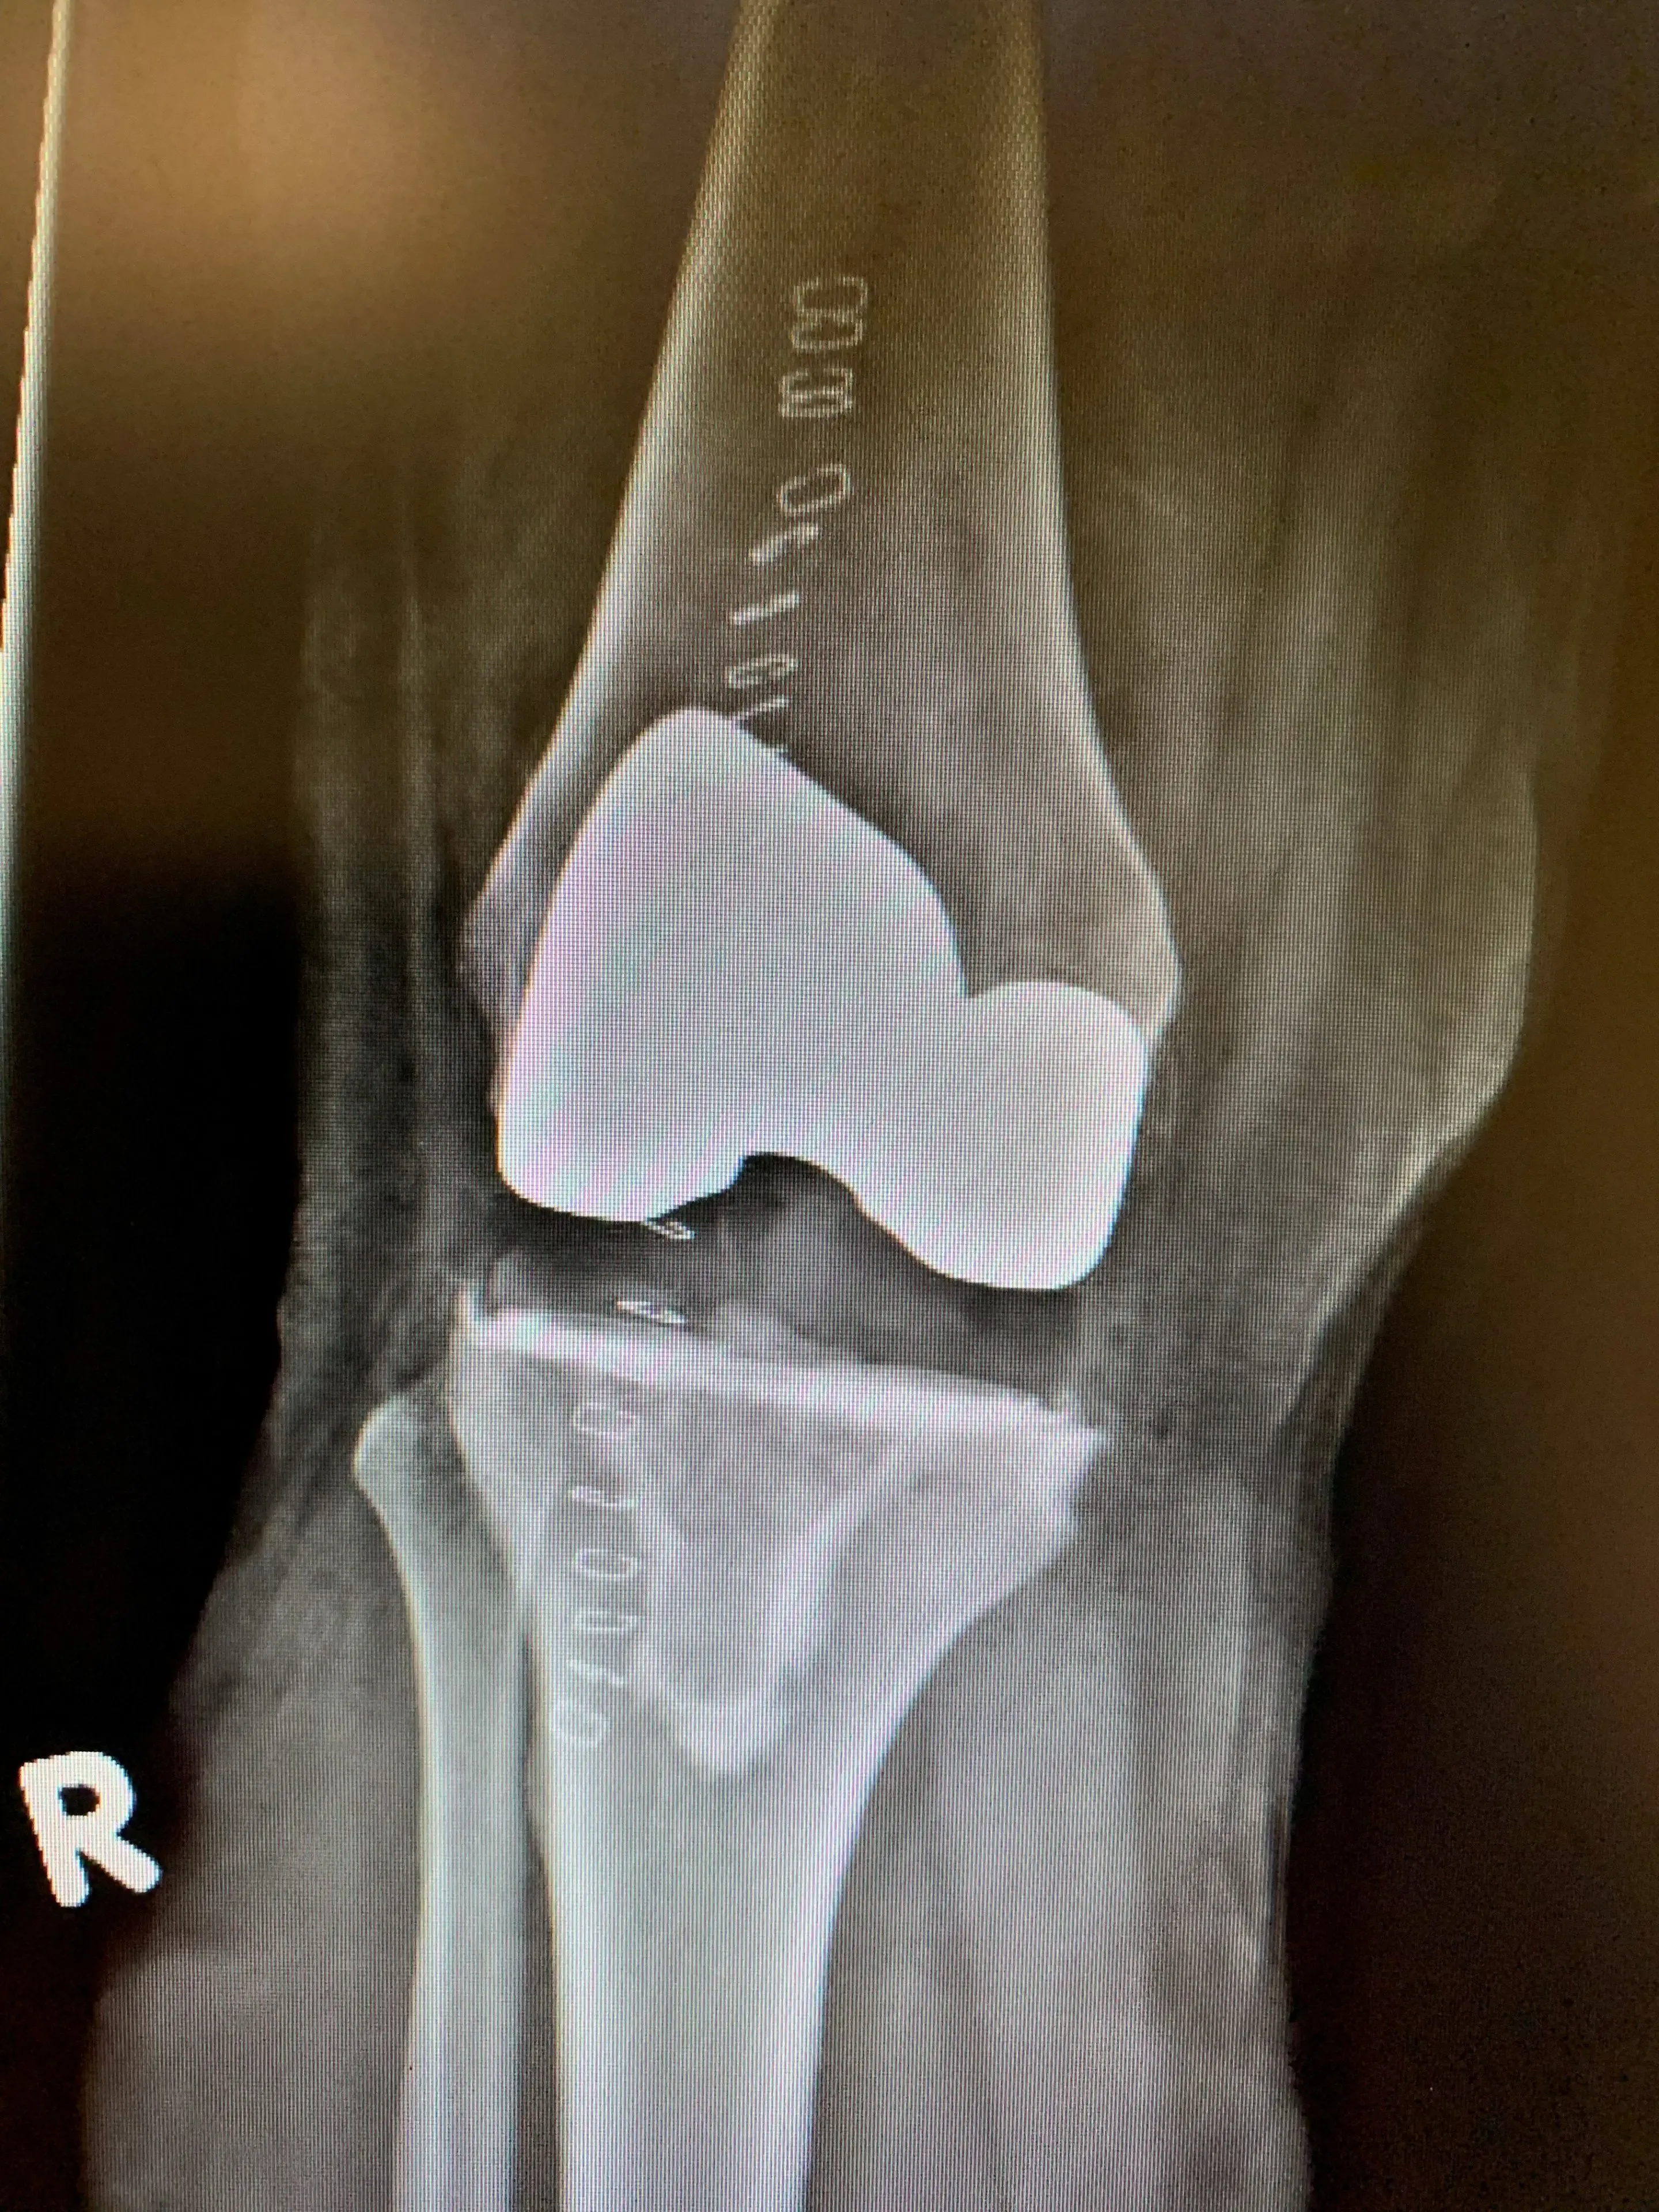

Post-op

Computer-navigated primary knee replacement.

Computer navigated primary knee-replacement